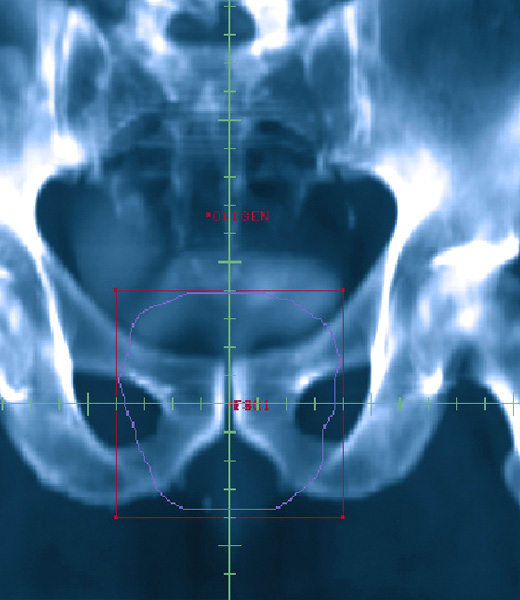

• Beam Eye View (BEV), o visión focal del haz permite visualizar los diferentes contornos delineados tal como se verían desde el foco del acelerador. Los físicos y dosimetristas usan esta herramienta para analizar las posibles incidencias de los haces de radiación para lograr la mejor vista del blanco evitando la irradiacion de la anatomía normal.

• Conformación automática de haces de tratamiento: usando el BEV junto con esta herramienta se puede generar un contorno alrededor del blanco dejando el margen necesario para lograr la cobertura dosimétrica del mismo, protegiendo los tejidos sanos.

• Digital Reconstructed Radiographs (DRR): Radiografías reconstruidas digitalmente. Esta herramienta del sistema, permite visualizar las diversas densidades tisulares, en cada angulación o BEV que se requiera, incluyendo la visión superpuesta de cada campo conformado.

Estas radiografías son de fundamental importancia para asegurar la calidad del tratamiento radiante a efectuar: permiten verificar que el tratamiento planificado está siendo entregado con una alta precisión, tanto por comparación con las placas de localización obtenidas en el simulador como por la comparación con las placas de verificación obtenidas en el equipo de tratamiento.

Se procede a la localización y verificación de todos los campos del paciente en una segunda simulación, utilizando para ello las radiografías reconstruidas digitalmente (DRR), tanto en las direcciones de haces de tratamiento, como localizadoras ortogonales.